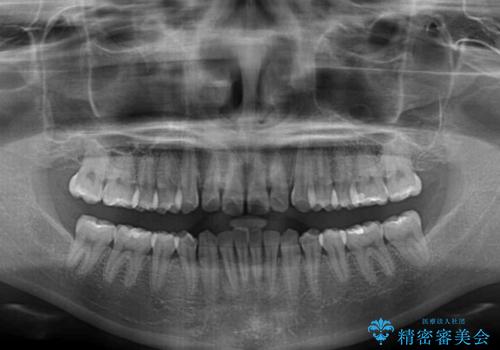

- 上顎前歯の隙間を気にして来院された患者様です。

下顎前歯が上顎前歯に食い込むような咬み合わせにより、上顎前歯が開いてしまっていたため、咬合高径の挙上により突き上げを改善するよう、インビザラインにより矯正治療を行うこととしました。

咬合高径の挙上により上顎前歯の突出感も改善することができ、整った口元となりました。